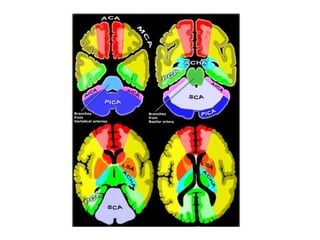

b) Cerebral Arterial Territory :

1-Posterior Inferior Cerebellar Artery

2-Superior Cerebellar Artery

3-Branches from vertebral and basilar artery

4-Anterior Choroidal artery

5-Lenticulostriate arteries

6-Anterior cerebral artery

7-Middle cerebral artery

8-Posterior cerebral artery

1-Posterior Inferior Cerebellar Artery (PICA in blue)

-The PICA territory is on the inferior occipital

surface of the cerebellum and is in equilibrium

with the territory of the AICA in purple which

is on the lateral side

-The larger the PICA territory , the smaller the

AICA and vice versa

2-Superior Cerebellar Artery (SCA in grey)

-The SCA territory is in the superior and tentorial

surface of the cerebellum

-The lateral LSA (in orange) are deep penetrating

arteries of the middle cerebral artery (MCA)

-Their territory includes most of the basal ganglia

-The medial LSA (indicated in dark red) arise from

the ACA (usually the A1 segment)

-Heubner's artery is the largest of the medial

lenticulostriate arteries and supplies the

anteromedial part of the head of the caudate and

anteroinferior internal capsule

-The territory of the lateral lenticulostriate

perforating arteries of the MCA is indicated

with a different color from the rest of the

territory of the MCA because it is a well-

defined area supplied by penetrating branches

which may be involved or spared in infarcts

separately from the main cortical territory of

the MCA

6-Anterior Cerebral Artery (ACA in red)

-The ACA supplies the medial part of the frontal

and the parietal lobe and the anterior portion

of the corpus callosum , basal ganglia and

internal capsule

7-Middle cerebral artery (MCA in yellow)

-The cortical branches of the MCA supply the

lateral surface of the hemisphere except for

the medial part of the frontal and the parietal

lobe (anterior cerebral artery) and the inferior

part of the temporal lobe (PCA)

-The deep penetrating LSA branches are

discussed before

8-Posterior cerebral artery (PCA in green)

-P1 extends from origin of the PCA to the posterior

communicating artery contributing to the circle

of Willis

-Posterior thalamoperforating arteries branch off

the P1 segment and supply blood to the midbrain

and thalamus

-Cortical branches of the PCA supply the

inferomedial part of the temporal lobe , occipital

pole , visual cortex and splenium of the corpus

callosum